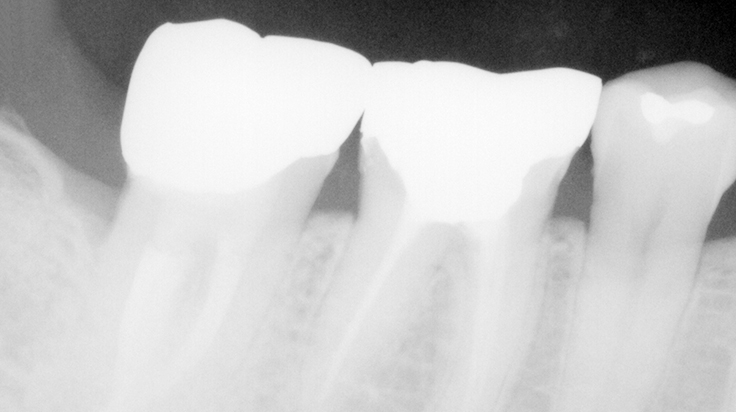

Crown lengthening (Posterior teeth)